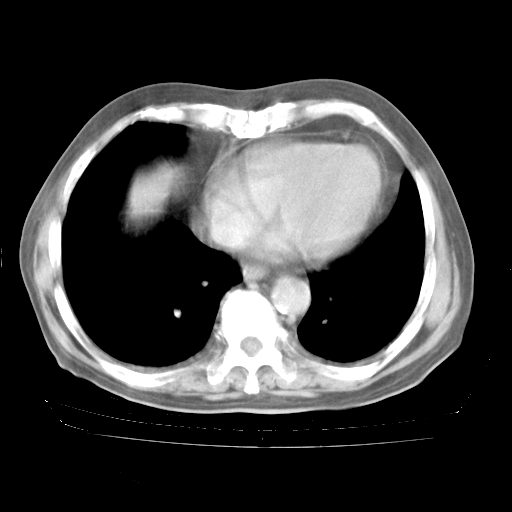

4月28日肺部CT——再次出现类似去年5月9日——透光度降低,“间质性”改变。

4月28日肺部CT——再次出现类似去年5月9日——磨玻璃样、间有“粟粒样”改变。

个人阅读4.14日肺部CT平扫:纵隔窗无异常,但肺窗示:双下肺内、后基底段有片絮状侵润影,部位以后基底段为著,以间质改变为主,呈急性肺泡炎征像,和首次住院影像学有相似之处。仅是个人读片,明日请相关专家再读片哈。其它建议同上。